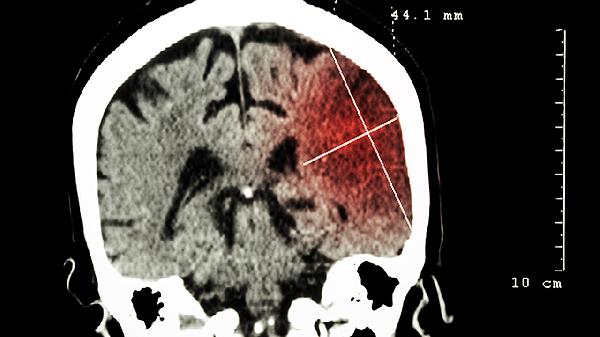

需要明确的是,中药不能作为治疗轻微脑瘤的主要方法。脑瘤的治疗核心取决于其病理性质、位置和大小,主要手段包括手术切除、放射治疗等。单纯依赖中药可能延误最佳治疗时机,导致肿瘤进展。中药的成分复杂,其抗肿瘤效果缺乏大规模临床研究的确切证据,无法达到手术根治或放疗控制的效果。因此,患者绝不能自行停用或替代医生制定的主要治疗方案,任何中药的使用都应在神经外科或肿瘤科医生的整体治疗框架下进行。